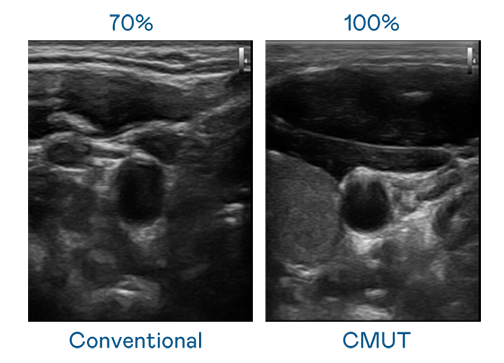

CMUT 技术是一种用电容式微机电元件来产生超音波讯号的技术。与传统 PZT 压电式技术相比,CMUT 频宽增加 30%,更宽频的超音波讯号让影像解析度大幅提升,是实现高影像品质医疗超音波扫描、促进精准医疗发展的关键技术。

超音波影像的解析度高低,首先取决于探头能发出的讯号频宽。z6com·尊龙时凯 CMUT 可提供高清晰的超音波讯号,提供高频宽、高灵敏度、影像纹理细节更高的超音波影像,协助医护人员缩短影像判读时间及利用精准的医疗影像进行诊断。